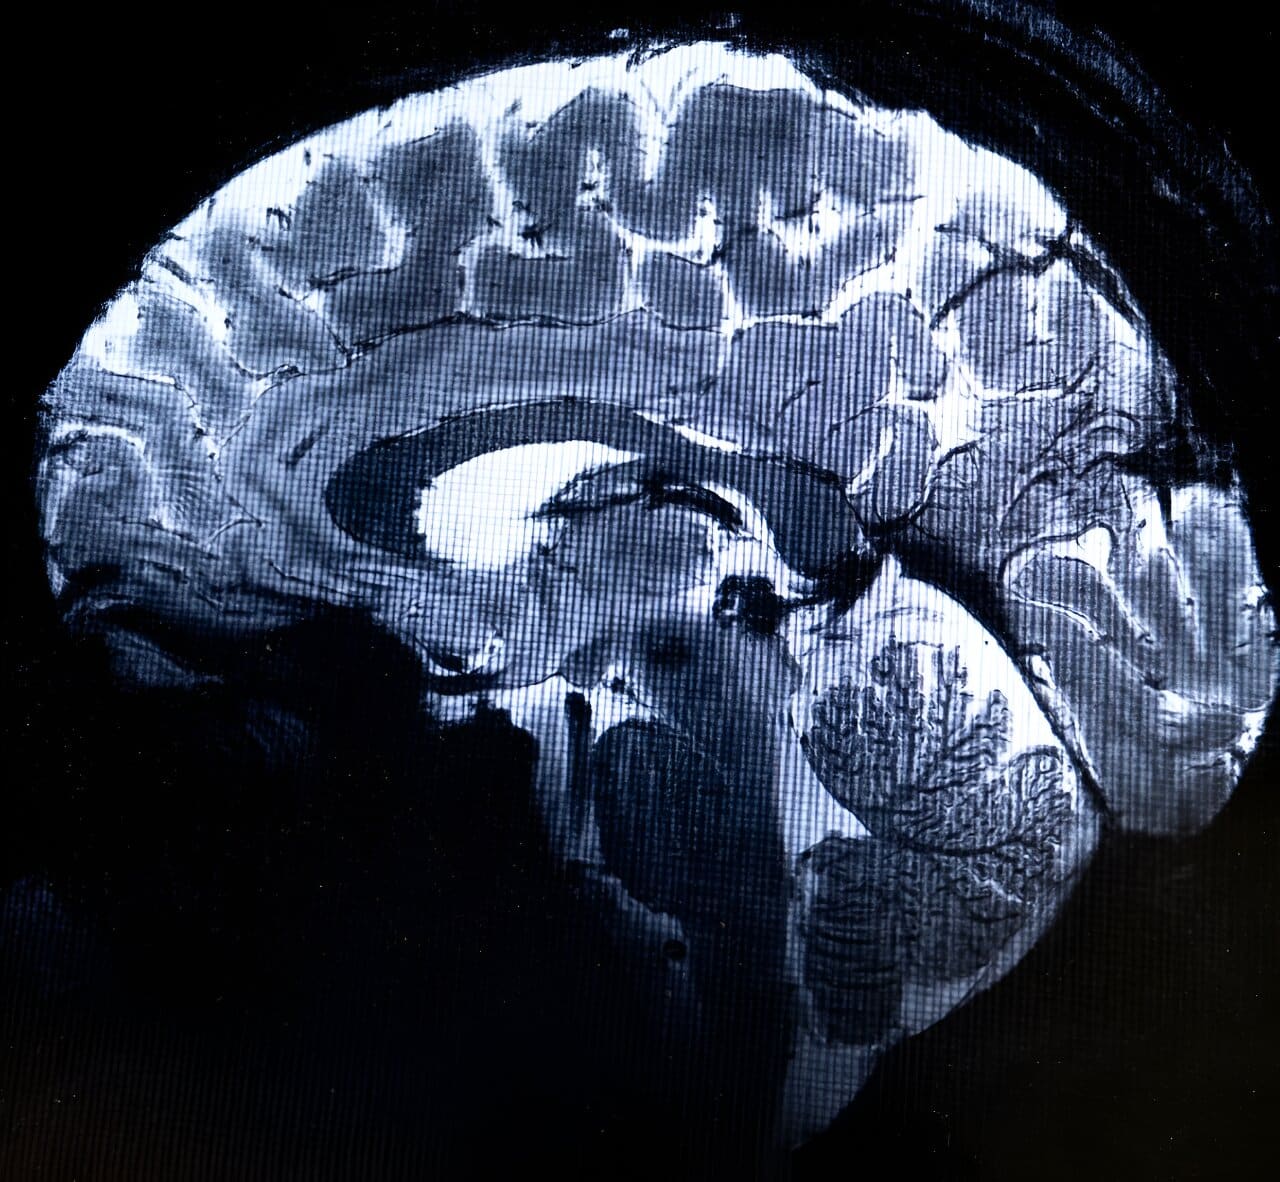

Найпотужніший у світі МРТ зробив перші зображення людського мозку

Наймогутніший у світі магнітно-резонансний томограф (МРТ) створив перші знімки людського мозку з десятикратною точністю порівняно зі звичайними